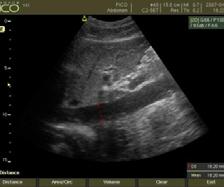

Patternuri de infiltrare a măduvei osoase în MM decelate prin IRM (figura )

Leziunile MM sunt prezente predominant în scheletul axial și anume vertebre (66%), pelvisul osos (30%) și într-o măsură mai mică la nivelul scheletului extra-axial (coaste, schelet apendicular) [20] În literatură sunt descrise cinci tipuri de infiltrare a măduvei osoase în mielomul multiplu: măduvă cu aspect normal, infiltrare focală a măduvei osoase, infiltrare difuză, infiltrare de tip “sare și piper” și infiltrare combinată focală și difuză [21, 22]; Există o multitudine de studii apărute în literatură care corelează aceste tipuri de infiltrare medulară cu modificările vizualizate la examenele morfo-patologice [23, 24]. În majoritatea cazurilor de MM (28%) se observă un aspect normal al măduvei osoase, cu hipersemnal T1 omogen al acesteia; în cazul infiltrarii, focale se observă diverse leziuni focale T1 hipointense, care pot apărea oriunde la nivelul scheletului; în cazul infiltrării difuze, se observă hiposemnal T1 difuz la nivelul intregii măduve osoase, uneori în caz de infiltrare severă, semnalul fiind chiar mai redus decât cel al discului intervertebral. În doar 3% din cazuri se observă un model de tip „sare și piper” și în 11% din cazuri se poate observa un model mixt de infiltrare nodulară și difuză [22, 25]

Tipuri de afectare medulară în mielomul multiplu: aspect normal imagistic(a), infiltrare focală(b), infiltrare difuză(c) infiltrare de tip ‘sare și piper’, infiltrare mixtă de tip focal și difuz(d). Departamentul de Radiologie al Spitalului Clinic Municipal de Urgență - Timișoara/RO